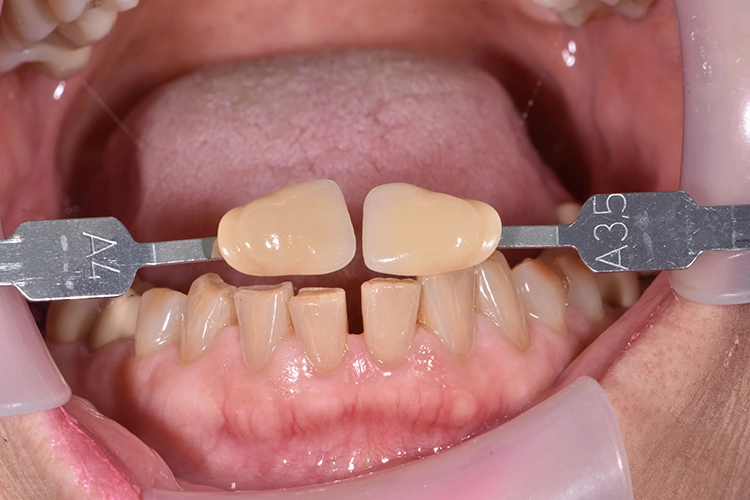

Bilder: Dr. Lampson / HannkerVor Beginn der Behandlung stand die Farbtonbestimmung (Abb. 4). Alte Kronen sowie Karies wurden entfernt, um anschließend mit Gænial® Universal Injectable (GC) den Stumpf aufzubauen und mit einer Hohlkehle zu präparieren (Abb. 5). Zur exakten Übertragung der Implantatposition an Position 47 erfolgte die Abformung mittels Pick-up-Technik.